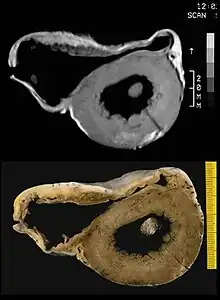

MRI in a patient affected by ARVC/D (long axis view of the right ventricle): note the transmural diffuse bright signal in the RV free wall on spin echo T1 (a) due to massive myocardial atrophy with fatty replacement (b).

In vitro MRI and corresponding cross section of the heart in ARVD show RV dilatation with anterior and posterior aneurysms (17-year-old asymptomatic male athlete who died suddenly during a soccer game).

Fatty infiltration of the RV free wall can be visible on cardiac MRI. Fat has increased intensity in T1-weighted images. However, it may be difficult to differentiate intramyocardial fat and the epicardial fat that is commonly seen adjacent to the normal heart. Also, the sub-tricuspid region may be difficult to distinguish from the atrioventricular sulcus, which is rich in fat.

Cardiac MRI can visualize the extreme thinning and akinesis of the RV free wall. However, the normal RV free wall may be about 3 mm thick, making the test less sensitive.